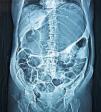

A 56-year-old woman was admitted to the emergency room with a one-day history of abdominal distension and epigastric pain. She started having symptoms after bowel preparation for colonoscopy. Abdominal CT scan showed an extremely distended stomach and small bowel (Fig. 1), as well as gas in the hepatic-portal veins (Fig. 2). Hepatic portal venous gas is a rare condition that occurs when intraluminal gas enters the portal venous circulation. Although there have been numerous reported causes, the majority are due to intestinal ischemia, with an estimated mortality rate of 75–80%. Mucosal barrier disruption of any kind can theoretically result in hepatic portal venous gas, but it appears to be more common in intestinal ischemia, inflammatory bowel disease, and peptic ulcer disease. Iatrogenic mucosal tears from endoscopy can also result in this situation. Diagnosis is usually made by plain abdominal radiography, sonography, color Doppler flow imaging, or computed tomography scan. An abdominal CT scan showed the classic sign of dilated vessels extending to within 2cm of the liver capsule, in contrast to biliary gas, which ends up collecting centrally as a result of the centripetal movement of bile.